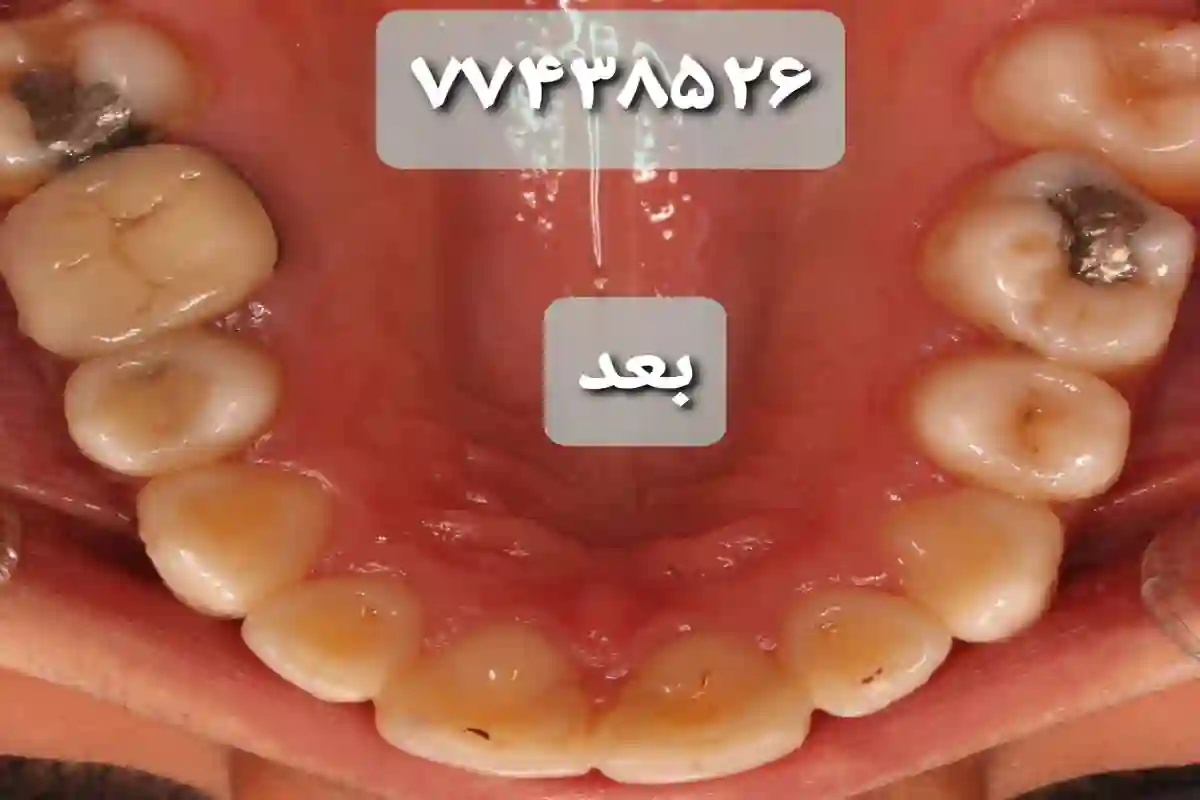

متخصص ارتودنسی (دکتر عاطفه صفار شاهرودی)

ارائه انواع درمان در مرکز تخصصی ارتودنسی دکتر عاطفه صفار شاهرودی . متخصص ارتودنسی و درمان ناهنجاری های فکی. هیئت علمی دانشگاه علوم پزشکی تهران. رتبه برتر آزمون بورد تخصصی . فارغ التحصیل از دانشکده دندانپزشکی دانشگاه تهران.